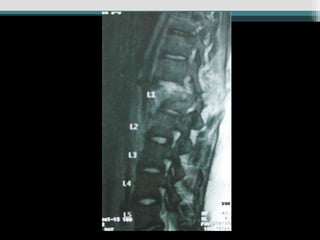

Caso 1 (34 anos, queda, Fk e)

Caso 2 (25 anos, auto, Fk a)

Caso 1 (34anos, queda, Fk e)

Caso 2 (25anos, auto, Fk a) www.traumatologiaeortopedia.com.b